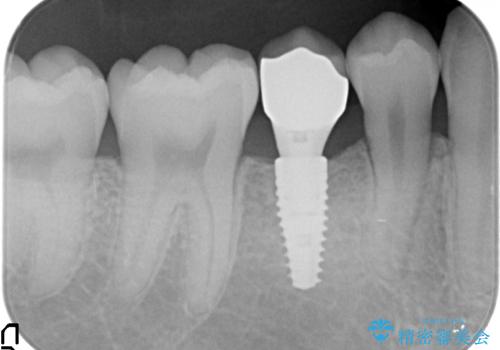

そのため、5番目のインプラントと、7番目の骨整形を同時に行い、整形で取れた7番目の骨をインプラント周囲に移植し、骨を増やすことにしました。

元々乳歯が残っていた場所であり、骨はたくさんあったため、インプラントを入れるのにそこまで支障はありませんでした。

ただし、奥歯の骨外科治療を同時に行うことで、同時についでに自分の骨を移植できるタイミングだったため行っておきました。